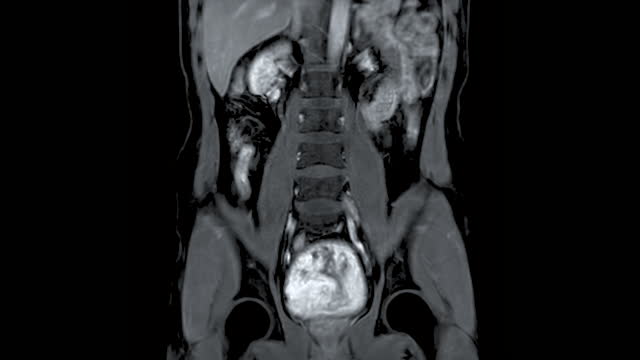

신장암은 흡연, 비만, 고혈압 등과 관련된 원인이 있을 수 있습니다. 그러나 암의 발생 원인을 규명하는 것보다 더 중요한 것은 조기 발견입니다. 신장암은 양쪽 신장에서 동시에 발견되는 경우가 드물며 대부분 한쪽에서 발견됩니다.

신장암이 조기에 발견되면 치료 가능성이 높아집니다. 이러한 조기 진단을 통해 작은 크기의 암이 발견되면 신장을 완전히 제거하지 않고 부분적으로 절제하는 수술이 가능하며, 이는 최근에는 로봇을 이용한 절제술로 더욱 효과적으로 수행됩니다.

신장암은 혈액 검사나 소변 검사로는 조기 진단하기 어렵습니다. 따라서 건강을 유지하고자 하는 목적으로는 초음파 검사를 적어도 일 년에 한 번 받는 것이 좋습니다. 초음파 검사를 통해 작은 크기의 신장암도 조기에 발견할 수 있습니다.